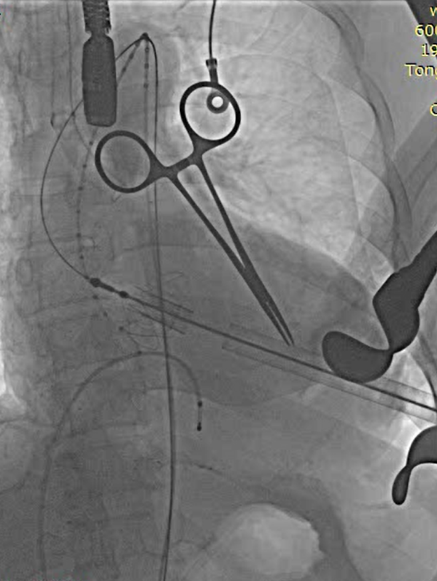

全麻后取仰卧位,消毒。取左前胸第5肋间切口进胸,腔镜辅助下游离左侧乳内动脉(LIMA)备用。肝素化。显露左前降支动脉(LAD),于其狭窄远段切开,将LIMA与之端侧吻合。血管桥排气后开放,测桥血流量满意。经股静脉植入心脏临时起搏器并确认正常工作。经股动脉置入造影导管至升主动脉根部,造影显示主动脉瓣大量反流,窦部结构可。3-0 Porlene线带毛毡片做荷包,经单弯导管引导超滑导丝至降主动脉,更换加硬导丝,导丝尖端于髂动脉分叉处。置入带主动脉瓣输送系统,造影定位下,准确释放29# J-Valve至主动脉瓣瓣环处,造影显示左右冠脉血流正常,TEE证实瓣膜位置可,未见明显反流。撤出输送系统,收紧荷包并缝合止血。放置胸管,逐层关闭各切口。

MICS-CABG

植入器进入升主动脉